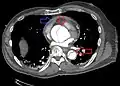

Computed tomography angiography is a fast, non-invasive test that gives an accurate three-dimensional view of the aorta. These images are produced by taking rapid, thin-cut slices of the chest and abdomen, and combining them in the computer to create cross-sectional slices. To delineate the aorta to the accuracy necessary to make the proper diagnosis, an iodinated contrast material is injected into a peripheral vein. Contrast is injected and the scan performed using a bolus tracking method. This type of scan is timed to injection to capture the contrast as it enters the aorta. The scan then follows the contrast as it flows through the vessel. It has a sensitivity of 96 to 100% and a specificity of 96 to 100%. Disadvantages include the need for iodinated contrast material and the inability to diagnose the site of the intimal tear.

- CT with contrast demonstrating aneurysmal dilation and a dissection of the ascending aorta (type A Stanford)

- Chest CT with descending (type B Stanford) aortic dissection (red circle)

- Type A dissection with pericardial effusion as a result.